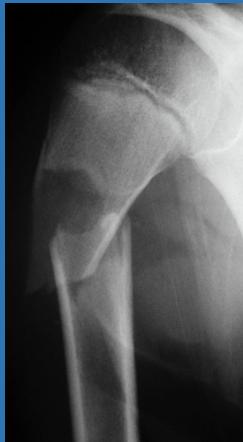

| Compartment Syndrome | Increased pressure within a closed fascial compartment, leading to reduced tissue perfusion, hypoxia, and irreversible muscle and nerve damage. Causes: Fractures (especially tibia/forearm), severe soft tissue trauma, arterial injury, burns, tight casts/dressings, post-ischemic reperfusion swelling, IV fluid extravasation, and bleeding disorders (e.g., hemophilia). High-Risk Notes: Pain may be absent in altered consciousness, children (monitor analgesia response), polytrauma, sedated/epidural cases, or concomitant nerve damage. Open fractures do not always decompress pressure. Gross/Clinical: -tense, shiny leg swelling with blisters in compartment syndrome.Imaging: - Intraoperative fasciotomy | History/Symptoms: Pain out of proportion to the injury (e.g., a “bursting” sensation), which is not relieved by analgesia. Clinical Features (The 5 P’s): - Pain with passive stretch (early, key sign; e.g., ankle dorsiflexion for leg, wrist for forearm). - Paresthesia (early). - Palpable tense swelling (shiny skin, blisters: clear=mild, serosanguinous=severe, bloody=worst; dusky/pallor skin). - Pallor, Paralysis, Pulselessness (late, ominous signs; pulses often palpable until late). Investigations: Primarily a clinical diagnosis (high suspicion key). Compartment pressure measurement can confirm: absolute pressure >30 mmHg or Delta Pressure (Diastolic BP - Compartment P) ≤ 25 mmHg. | Initial: ABCs, supplemental oxygen. Remove all circumferential dressings, casts (bivalve to skin), and splints. Elevate the limb to heart level (not above; higher reduces inflow). Correct any hypotension. Surgical: Urgent Fasciotomy if no response within 1h or confirmed pressure (prophylactic in high-risk like major osteotomy). Release all compartments/skin with long incisions; debride necrotic muscle via 4C’s (early: pink/red, soft, contracts/bleeds on pinch; late: dark, firm, no response); preserve neurovascular. Wound open (bulky dressing/splint, VAC, or boot-lace gradual closure); repeated inspections x48h; coverage in 3-5 days (skin graft usual; flap if nerves/vessels/bone exposed). | Cellulitis, Deep Vein Thrombosis (DVT), Arterial occlusion, Severe soft tissue injury without compartment syndrome; equivocal cases in polytrauma. | Complications: Volkmann’s ischemic contracture (permanent deformity, weakness, sensory loss, chronic pain). Contraindications (Fasciotomy): Confirmed >48h (irreversible damage, high infection risk from dead tissue); crush injuries with already necrotic muscle. |